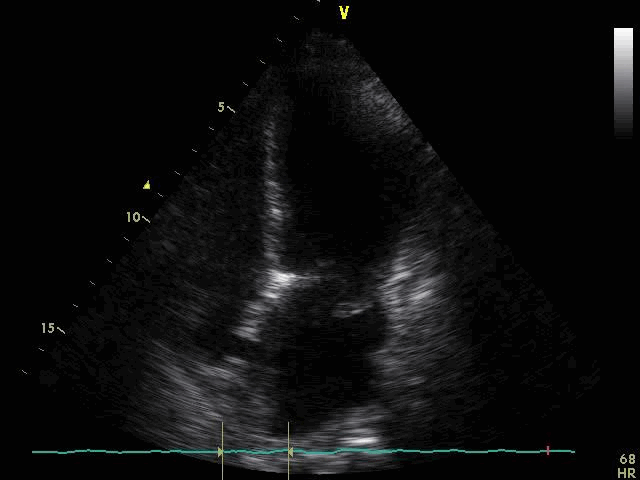

По данным трансторакальной эхокардиографии (ЭхоКГ) визуализировалось пролабирование передней створки митрального клапана в полость левого предсердия (рисунок 2).

Отмечалось незначительное увеличение полости левого предсердия в отсутствие увеличения полостей правого и левого желудочков, а также повышенная сократительная способность миокарда левого желудочка (ЛЖ) без признаков нарушения локальной сократимости миокарда, глобальная фракция выброса ЛЖ достигала 65% (рисунок 3).